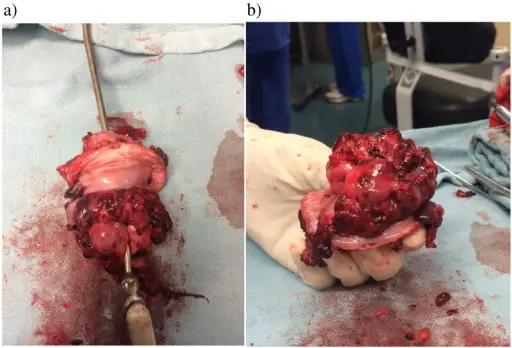

Rhabdomyosarcomas are malignant tumors composed mainly of skeletal muscle.

Rhabdomyomas typically effect skeletal muscle, or occasionally hollow organs like the bladder or uterus.

Diagnosis is made by histology showing malignant skeletal muscle with rhabdomyoblasts, which are the characteristic cells of rhabdomyosarcoma.

Pathology stains for rhabdomyosarcoma will be desmin stain positive.

Rhabdomyosarcomas often involve the head and neck in the majority of patients, but the vagina is the classic site in young girls.